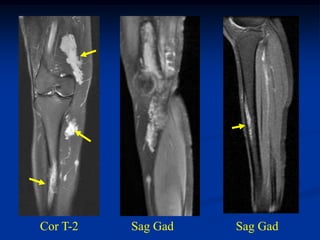

The myxoid variant is the most common variant of the lipo-

sarcoma and it is seen in a slightly younger age group between 40

and 50 years of age. It occurs in the lower extremities in 75% of

cases, especially in the popliteal area. These lesions are slow

growing and frequently asymptomatic in the early stages. On

imaging studies, the MRI is the best method for visualizing these

tumors that will have a mixed high and low signal on the T-1

weighted image because of the high percentage of fatty tissue in

the tumor. Histologically, there will be evidence of malignant

lipoblasts and it is common to find a plexiform network of small

capillary tubes running thru the fatty tumor, similar to the capillary

hemangioma. The prognosis for this variant is quite good after a

wide local surgical resection, followed in most cases by local

radiation therapy. The chance of pulmonary metastases runs as

high as 20% and occasionally there will be multifocal myxoid

liposarcomas occurring in the extremities as well as in retro-

peritoneal locations. Occasionally, one will see a transitional

form of myxoid converting into a higher grade round cell lipo-

sarcoma which carries a more guarded prognosis.

Myxoid Liposarcoma The myxoid variant is the most common variant of the lipo- sarcoma and it is seen in a slightly younger age group between 40 and 50 years of age. It occurs in the lower extremities in 75% of cases, especially in the popliteal area. These lesions are slow growing and frequently asymptomatic in the early stages. On imaging studies, the MRI is the best method for visualizing these tumors that will have a mixed high and low signal on the T-1 weighted image because of the high percentage of fatty tissue in the tumor. Histologically, there will be evidence of malignant lipoblasts and it is common to find a plexiform network of small capillary tubes running thru the fatty tumor, similar to the capillary hemangioma. The prognosis for this variant is quite good after a wide local surgical resection, followed in most cases by local radiation therapy. The chance of pulmonary metastases runs as high as 20% and occasionally there will be multifocal myxoid

liposarcomas occurring inthe extremities as well as in retro- peritoneal locations. Occasionally, one will see a transitional form of myxoid converting into a higher grade round cell lipo- sarcoma which carries a more guarded prognosis.